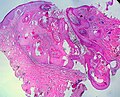

|

Keratoacanthoma. H&E stain. | |

| LM | keratin plug, downward cupping of the epidermis, minimal keratinocyte atypia, +/- keratinocytes with glassy pink cytoplasm |

- Expansion of stratum spinosum - pushing tongue-like downward growth of epidermis into the dermis.

- Keratin collection ("keratin plug") at the center of lesion-superficial aspect.

- Cells have glassy pink cytoplasm.

- Minimal/no nuclear atypia.

- Classically described as a "volcano lesion" with pale pink cells.

The sections show hair-bearing skin with a dome-shaped lesion that consists of a cup-shaped epidermal rim, and a large plug of keratin. The lesion is surrounded by a mild patchy lymphoplasmacytic infiltrate. No mitotic activity is apparent. The keratinocytes have minimal atypia and mature to the surface. A granular layer is present. The lesion is completely excised in the plane of section.

There is no hypergranulosis. No koilocytes are seen. Solar elastosis is present.